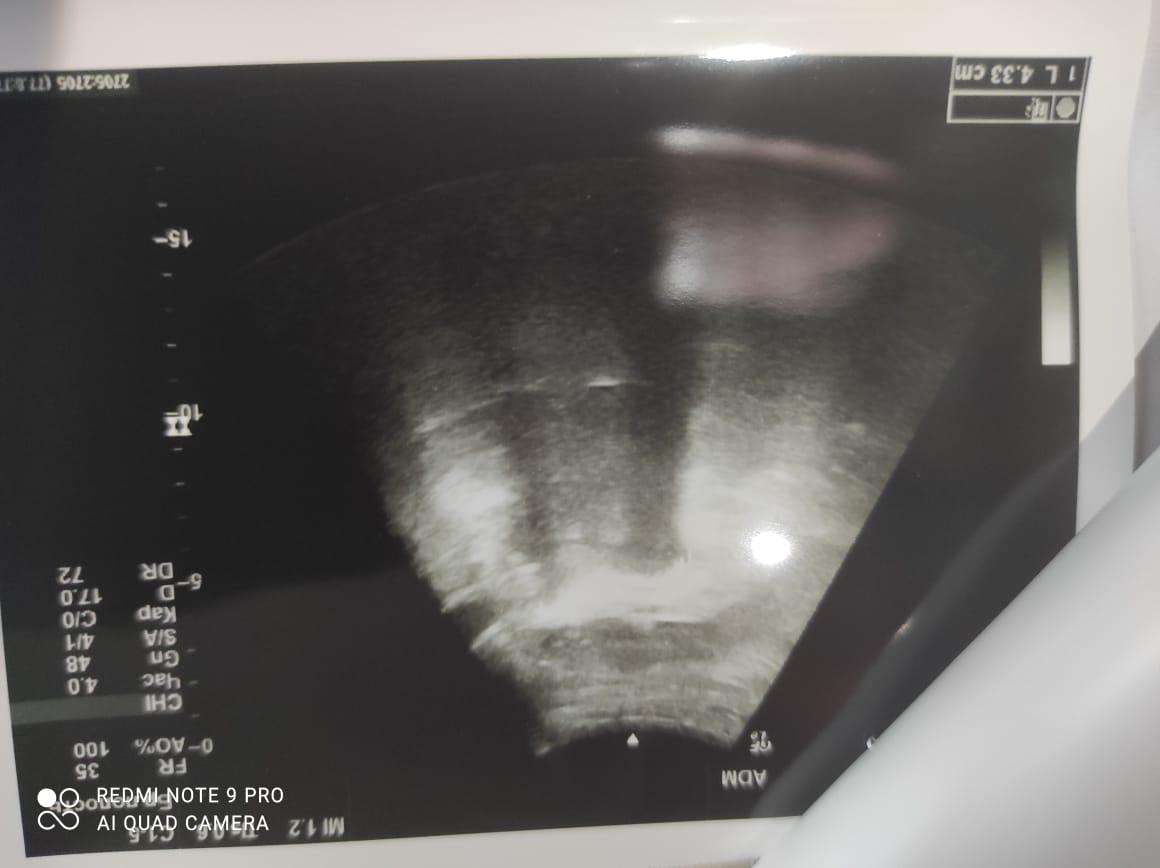

Здравствуйте! При наличии коралловидного камня правой почки(заключение УЗИ), можно предположить причиной боли нарушение уродинамики верхних мочевых путей), что, однако, не подтверждается результатами УЗИ почек( ЧЛС не расширена). Другая, наиболее вероятная возможная причина "боли в боку" - может быть патология опорнодвигательного аппарата. Необходимо проконсультироваться с неврологом и урологом очно, и согласовать возможность применения противовоспалительных, обезболивающих и спазмолитических препаратов - как первый шаг. В дальнейшем необходимо планировать возможное дальнейшее обследование и лечение. Удачи!